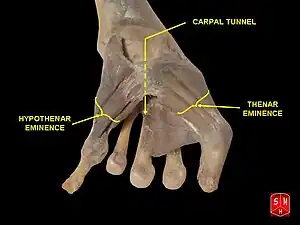

Wrist joint, deep dissection. Anterior palmar view. Carpal tunnel and thenar and hypothenar eminences

Carpal tunnel and thenar and hypothenar eminences Carpal tunnel